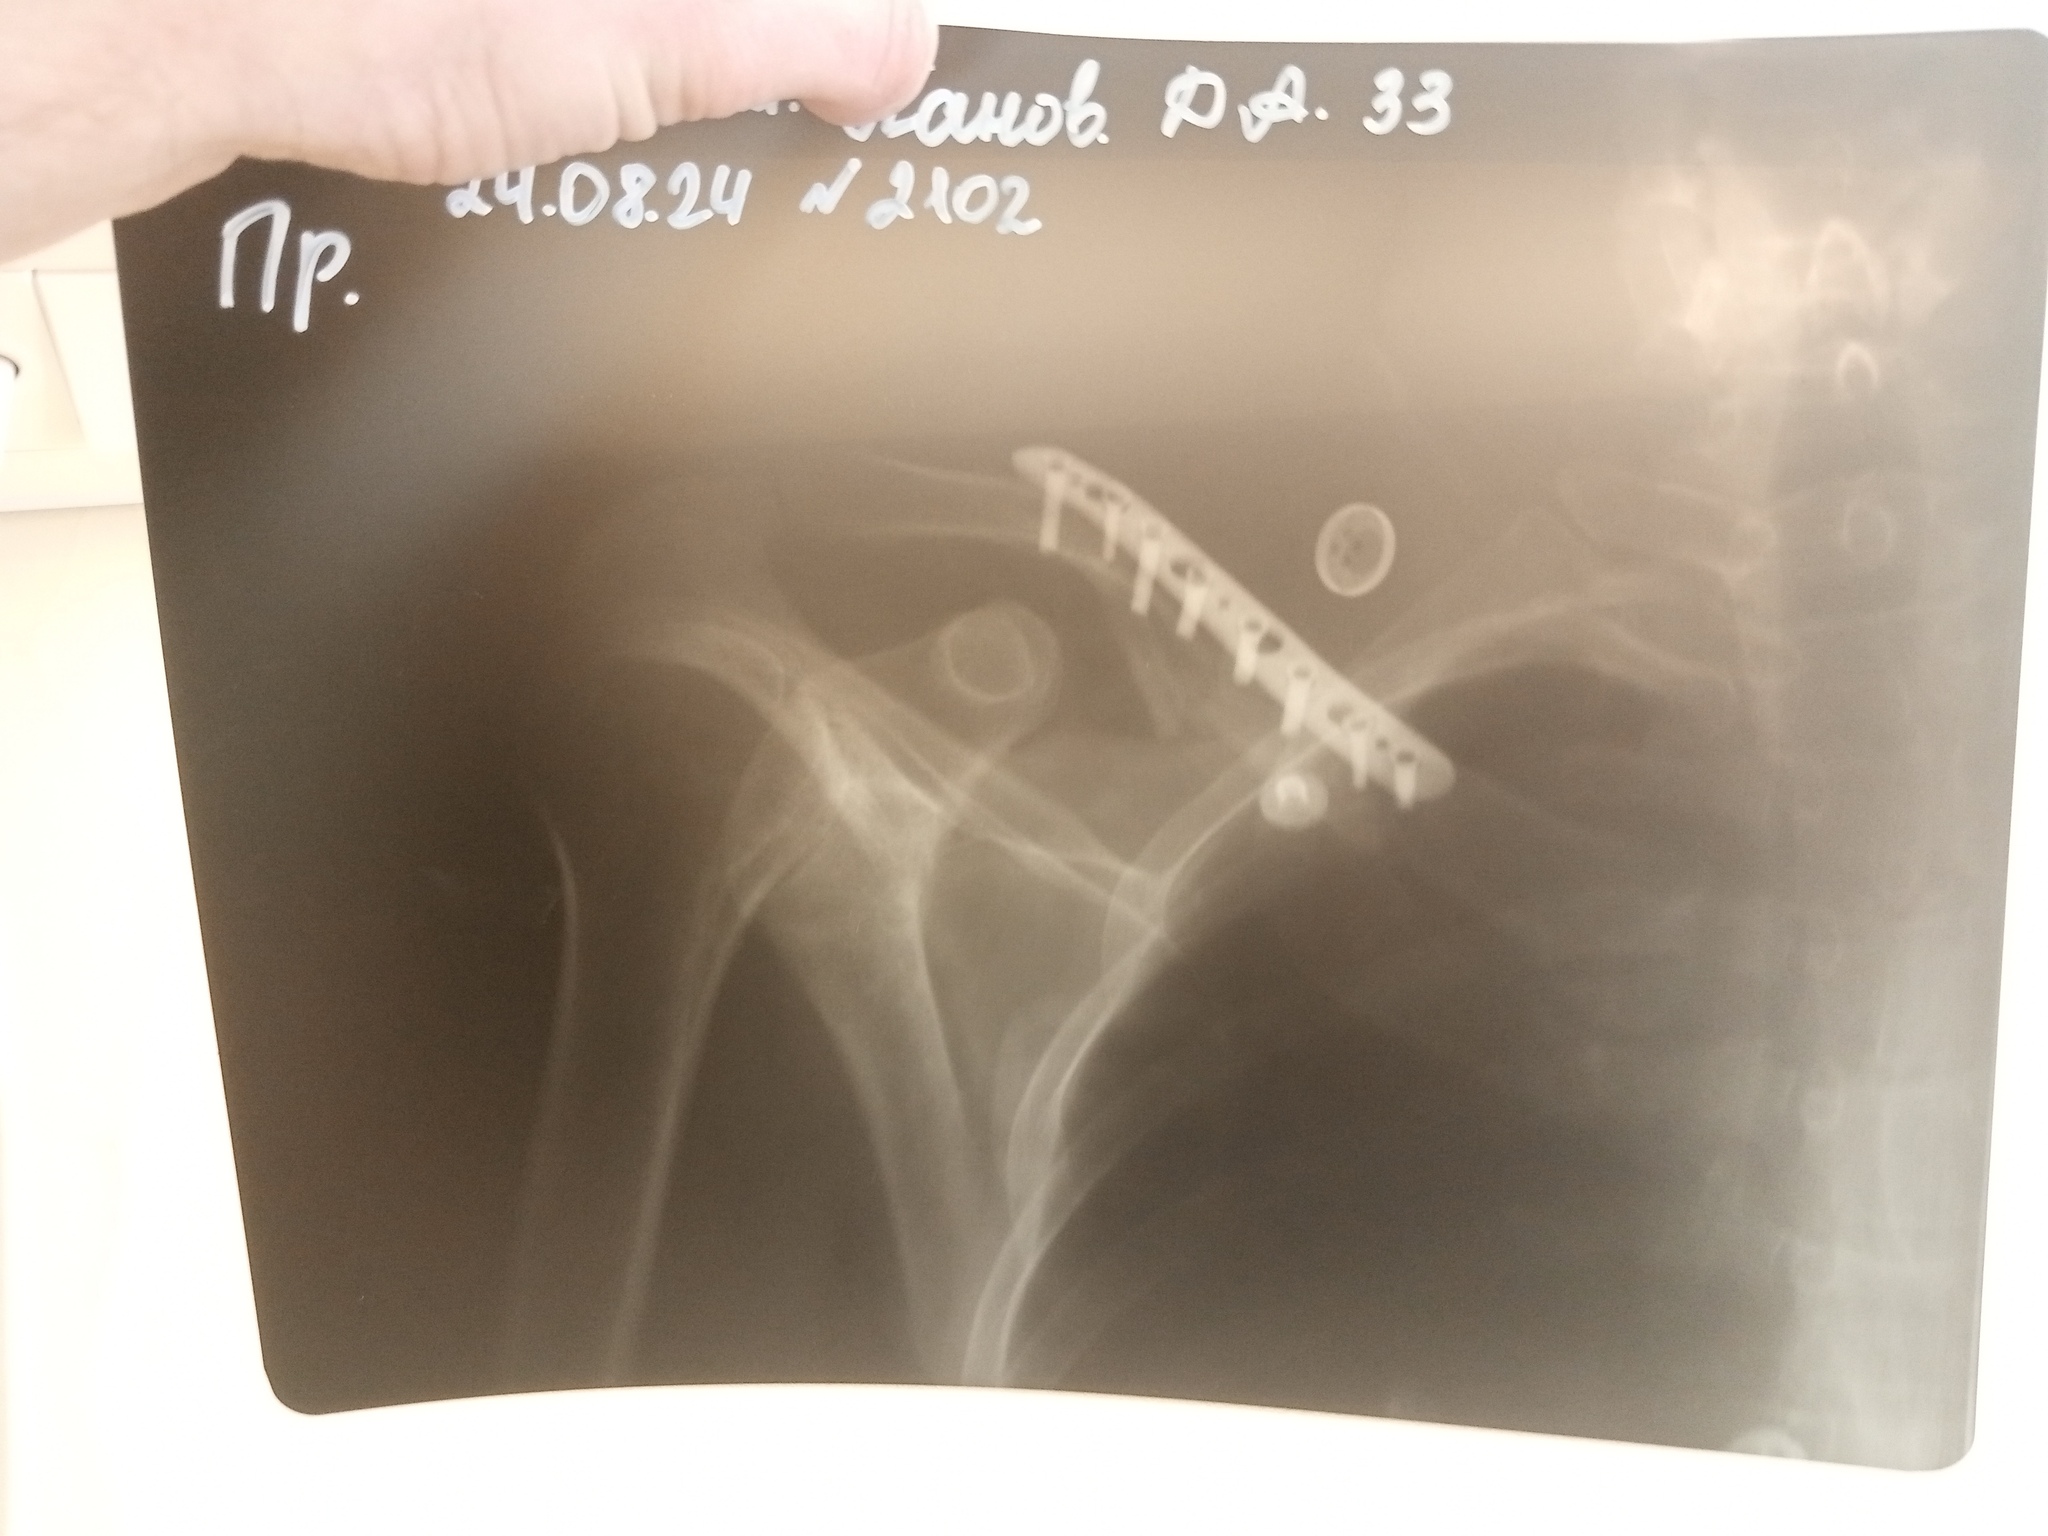

Продолжаем пропитываться народной мудростью и залихватски петь о том, что происходит вокруг. А вокруг меня сейчас происходит больничный и восстановление после остеосинтеза плеча (это когда разломанные кости собирают в монолит, обогащая организм железкой и винтами). Так что как бы ни хотелось, а байки из секс-шопа теперь с уклоном в область травматологии. Но! Наш народ такой ерундой не победить и на днях была поднята тема предстоящей человеку операции, что натолкнуло на написание этого поста Перед операцией и после неё мне отсыпали советов от товарищей, которые частично или полностью смонтированы на пластинах, винтах, скобах, штырях и прочем металле. От насоветованного и перспектив у меня теперь седина во всех местах, но избежать многих неприятностей они мне помогли. Плюс мои наблюдения и полученный лично опыт.